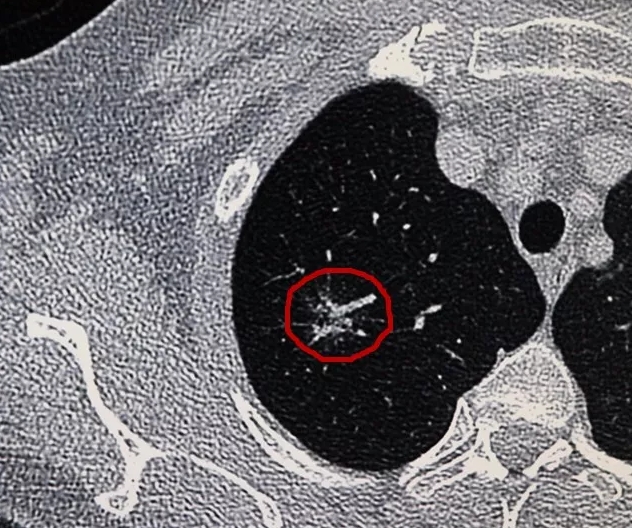

2019年1月28日,对于严女士来说是难过的一天,听说淄博市第四人民医院开展了早期肺癌低剂量螺旋CT筛查,她便来到医院做了一次胸部的CT,但检查报告显示有肺部结节。

淄博市第四人民医院自2018年3月正式开展早期肺癌低剂量螺旋CT筛查至今一年来,共筛查2278人次,诊断疑似病例49例,33例病理证实早期周围型肺腺癌,约占1.5%。